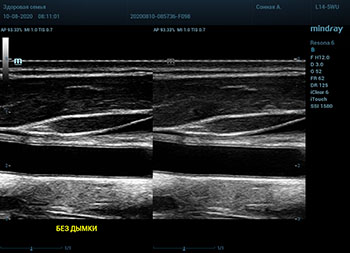

В приборах серии Resona, компании Mindray, появилась новая функция постобработки изображения. Имя ей Dehaze. В переводе на наш родной язык – удаление дымки или рассеивание тумана. Инструмент позволяет корректировать интенсивность тумана или дымки. При этом сохраняется общий контраст и детализация картинки. Dehaze также позволяет проявлять детали снимка в гиперэхогенных зонах и снимать артефакты при чрезмерном усилении.

Готовый снимок или видео петля в формате DICOM несет в себе полное нативное изображение. Прибор позволяет, подобно легендарному фотошопу, удалить лишний «туман». Гиперэхогенный диффузный «засвет» изображения, из-за повышенного общего усиления, часто вредит обследованию. Однако без него некоторые вещи не видны. Показать гипоэхогенные участки и скрыть эхогенную дымку и позволяет Dehaze.

Всё что требуется от доктора – нажать кнопку или повернуть ручку. Мгновенная оптимизация. Мгновенно чистое изображение.